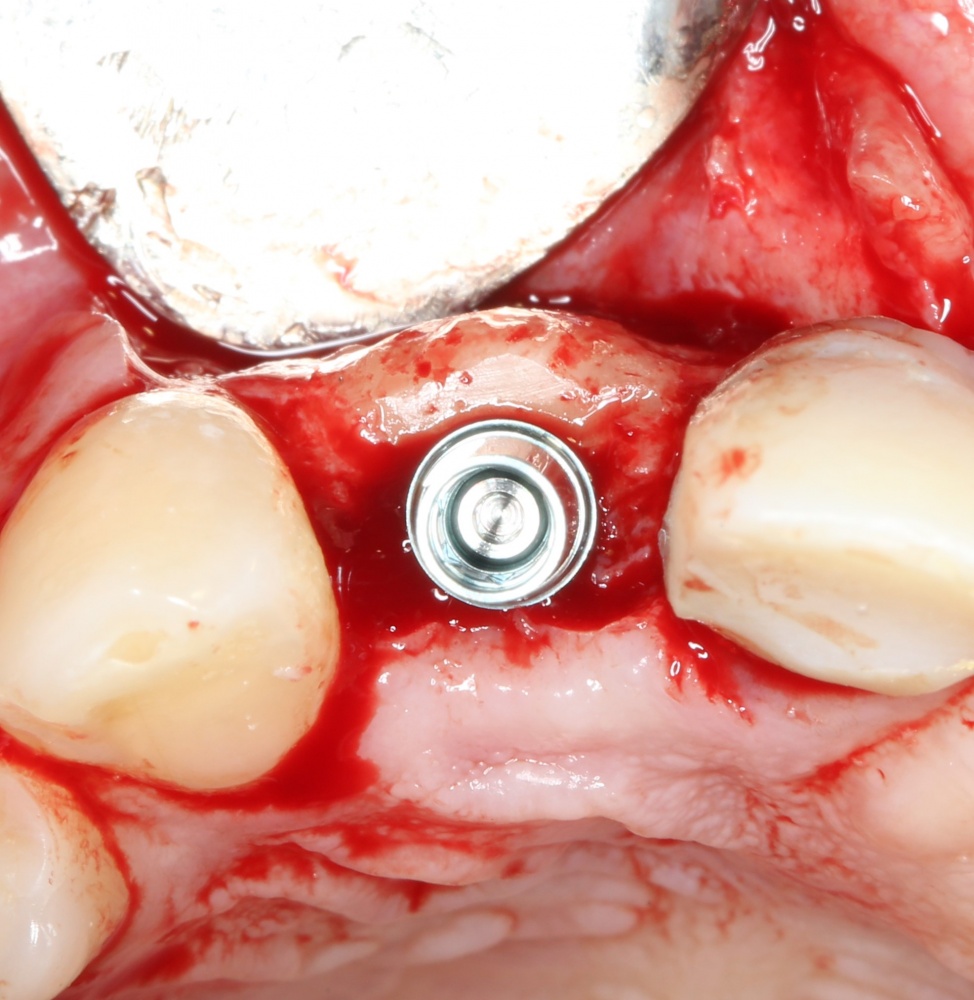

Кстати, обрати внимание на ширину альвеолярного гребня (левая картинка). Она чуть меньше 3 мм. Это объясняет, почему я засомневался в возможности установки имплантатов одновременно с остеопластикой. Понятно и без КЛКТ.

Возвращаемся к основной операционной области. Еще раз посмотрим на альвеолярный гребень, поофигеваем от его ширины и моих грандиозных планов: